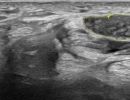

Hand Ultrasound is a simple and painless examination that does not require any preparation from the patient. Gel is applied to the patient's skin, and using a high-frequency ultrasound transducer, the radiologist conducts the examination.